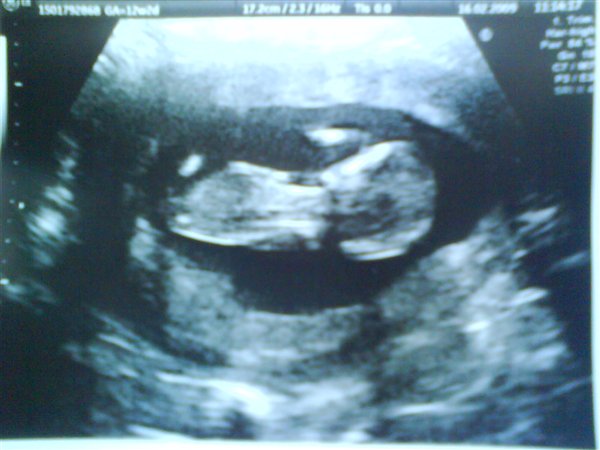

Jeg følte mig først rigtig gravid da jeg så den lille på skærmen. Men det har nok meget at gøre med at det tog os 8 år om at blive gravid, og så var den der pludselig. og så tænkte jeg næsten hver dag , kan det virkelig være rigtig, så derfor var scanningen det endelig bevis

Knus sabrina 13+0